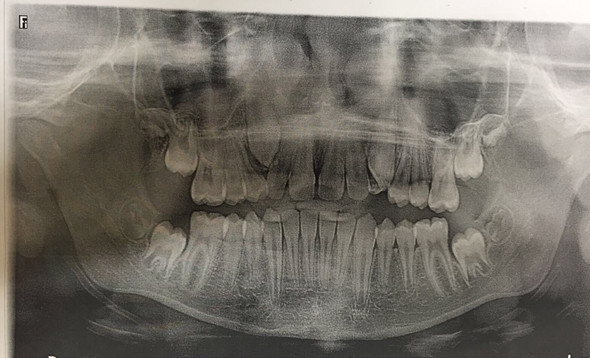

Neben den üblichen Zahnerkrankungen wie Karies, Pulpitis und apikaler Ostitis ist der obere Eckzahn sehr häufig retiniert und verlagert.

Ursache dafür ist die relativ späte Durchbruchszeit mit elf Jahren. In diesem Alter ist der Knochen bei manchen Kindern schon recht fest. Außerdem sind die bleibenden Nachbarzähne (zweiter Schneidezahn und erster Prämolar) schon vor dem Eckzahn da und können bei ausgeprägtem Platzmangel den gesamten Platz für den verspätet durchbrechenden Eckzahn einnehmen. Eventuell bricht der Eckzahn wegen Platzmangel auch weiter vestibulär durch – außerhalb der Zahnreihe. Er ragt dann wie ein Tigerzahn aus der vestibulären Wand des Alveolarfortsatzes.

Relativ häufig liegt der retinierte Eckzahn quer im Oberkieferknochen impaktiert.

Eine weitere Ursache für die Retention ist, dass der Eckzahn während seiner Bildungphase relativ weit oben im Kieferknochen liegt und einen sehr weiten Weg bis zum Zahndurchbruch zurücklegen muss.

Nach den Weisheitszähnen sind die Eckzähne die am zweithäufigsten betroffenen Zähne, die retiniert und verlagert sind. Ein persistierender Milch-Eckzahn im Oberkiefer deutet auf einen retinierten Eckzahn hin. Eine Nichtanlage der Eckzähne ist jedoch nicht bekannt bzw. extrem selten. Im Gegensatz dazu ist bei den Weisheitzähnen eine Nichtanlage häufig (ca. 50 %) und bei den benachbarten zweiten Schneidezähnen des Oberkiefers gelegentlich (ca. 1 %, familiär gehäuft) anzutreffen.

Die retinierten und verlagerten oberen Eckzähne werden bei Erwachsenen meist aus kieferorthopädischer Indikation operativ entfernt (meist mit palatinalem OP-Zugang). Bei Jugendlichen und bei günstiger vestibulärer Retentionslage wird die Zahnkrone operativ freigelegt und nach Wundheilung mit Hilfe eines aufgeklebten Brackets und festsitzendem oder herausnehmbarem KFO-Gerät eingestellt. Hierbei werden sowohl Multibandapparaturen als auch einfachere KFO-Geräte verwendet. Dazu muss in einigen Fällen durch Oberkieferdehnung (KFO) genügend Platz geschaffen werden. Der Zahn wird am Bracket angeschlungen und im Verlaufe einiger Monate oder Jahre meist mit Erfolg voll in die Zahnreihe integriert.

Untere Eckzähne sind weniger oft retiniert und verlagert als obere.